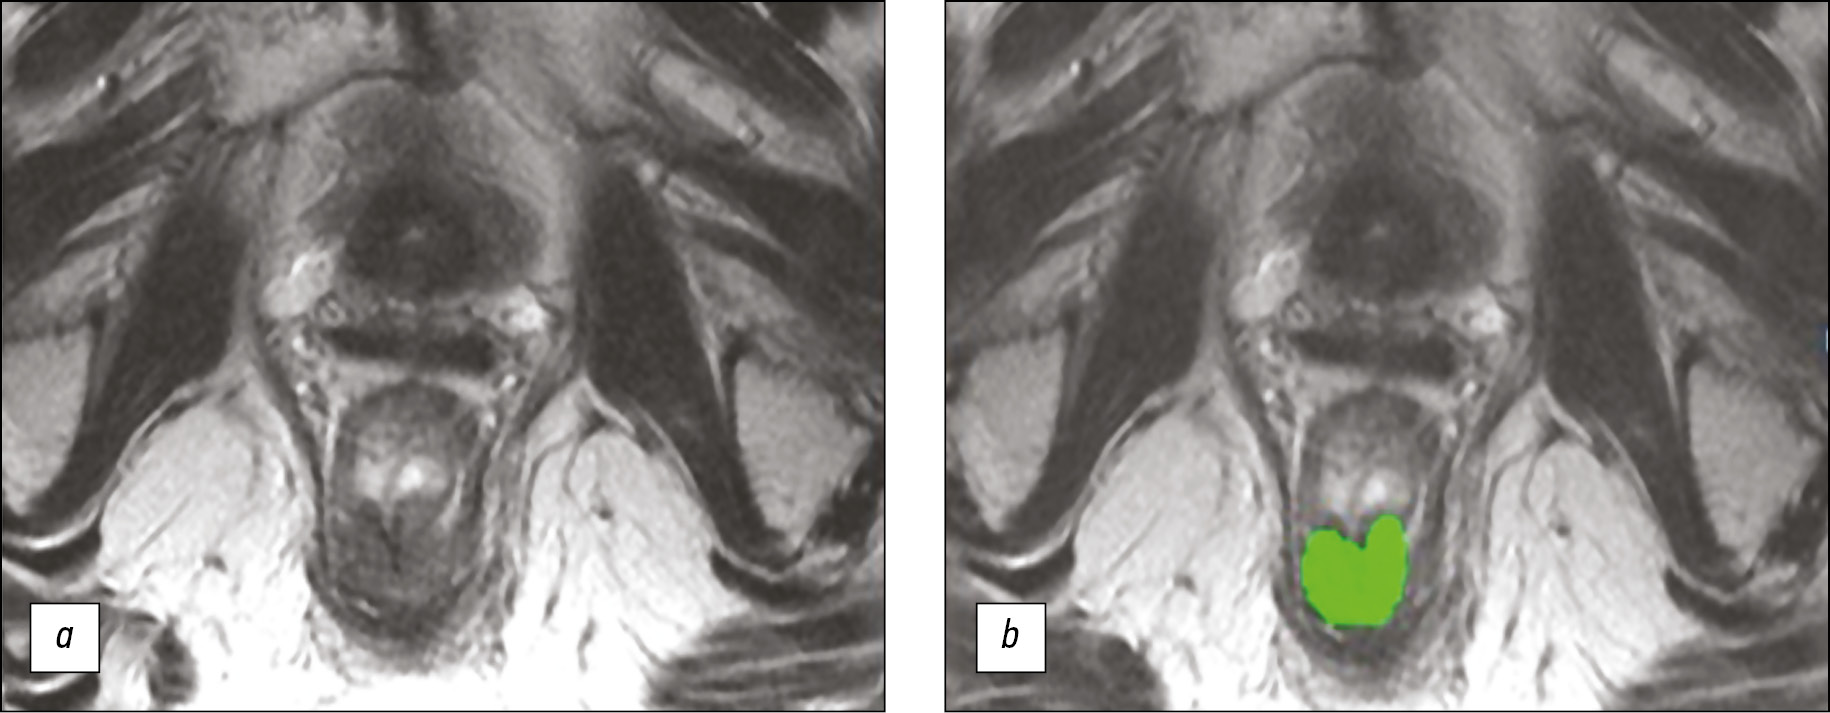

Another MRI examination of the pelvic organs did not reveal any deterioration (Fig. 4). However, given the difficulties of standard MRI in differentiating fibrosis and tumor tissue, T2-WI texture analysis was performed using the MaZda ver. 4.63 computer program based on a gray-level co-occurrence matrix [3]. Our scoring system was used to interpret the obtained parameters of texture analysis [4]. In particular, if the sum of the points of the five parameters of texture analysis is ≥3, then the patient responded to NHRT; otherwise, the patient did not respond to NHRT. The results of the texture analysis of this patient and the assessment criteria are presented in Table 1. Texture analysis indicated no signs of tumor progression.

Fig. 4. Magnetic resonance imaging of the tumor of the lower ampullar rectum 3 years after neoadjuvant chemoradiation therapy: a ― T2-WI; b ― segmentation of the zone of interest for texture analysis (highlighted in green).